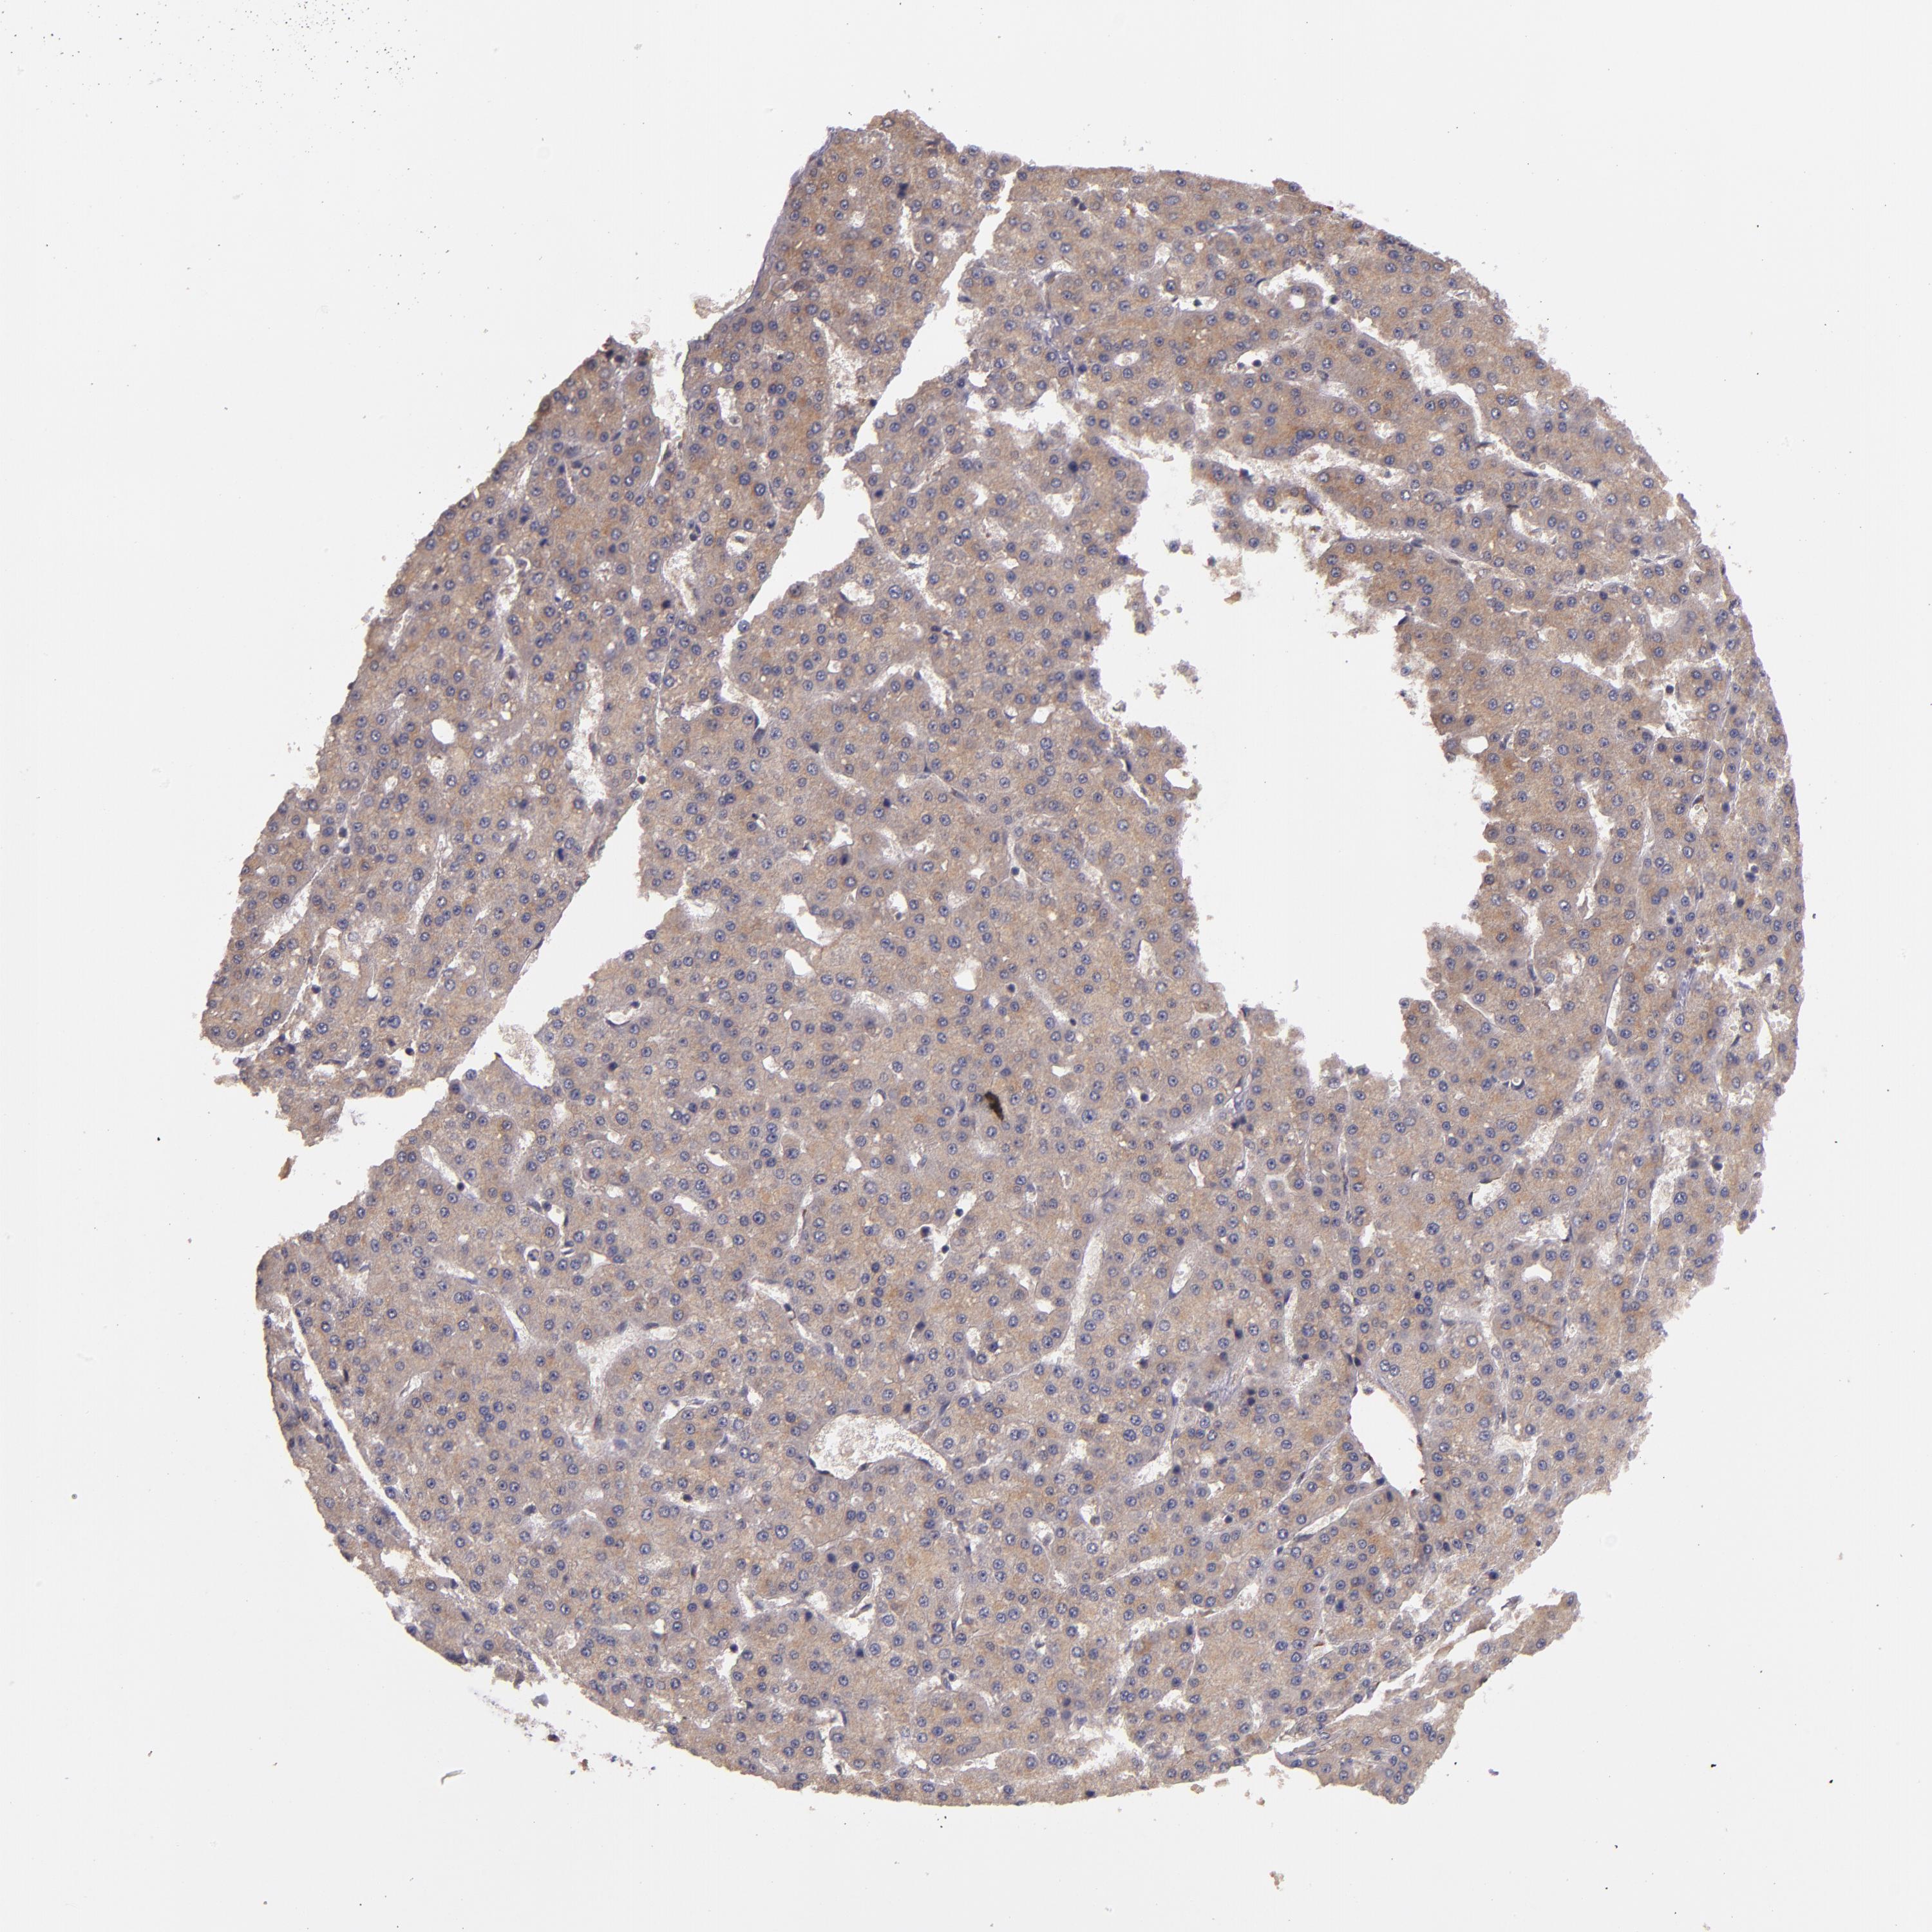

LIVER CANCER - Protein expressioni

A mouse-over function shows sample information and annotation data. Click on an image to view it in a full screen mode. Samples can be filtered based on level of antibody staining by selecting one or several of the following categories: high, medium, low and not detected. The assay and annotation is described here.

Note that samples used for immunohistochemistry by the Human Protein Atlas do not correspond to samples in the TCGA dataset.

Antibody stainingi

Antibody staining in the annotated cell types in the current human tissue is reported as not detected, low, medium, or high, based on conventional immunohistochemistry profiling in selected tissues. This score is based on the combination of the staining intensity and fraction of stained cells.

Each image is clickable and will lead to virtual microscopy that enables deeper exploration of all samples and also displays staining intensity scores, fraction scores and subcellular localization as well as patient and tissue information for each sample.

Antibody HPA002859

Antibody CAB011655

Staining

High

Medium

Low

Not detected

Intensity

Strong

Moderate

Weak

Negative

Quantity

>75%

75%-25%

<25%

None

Location

Nuclear

Cytoplasmic/membranous

Cytoplasmic/membranous,nuclear

Carcinoma, Hepatocellular, NOS

Cholangiocarcinoma